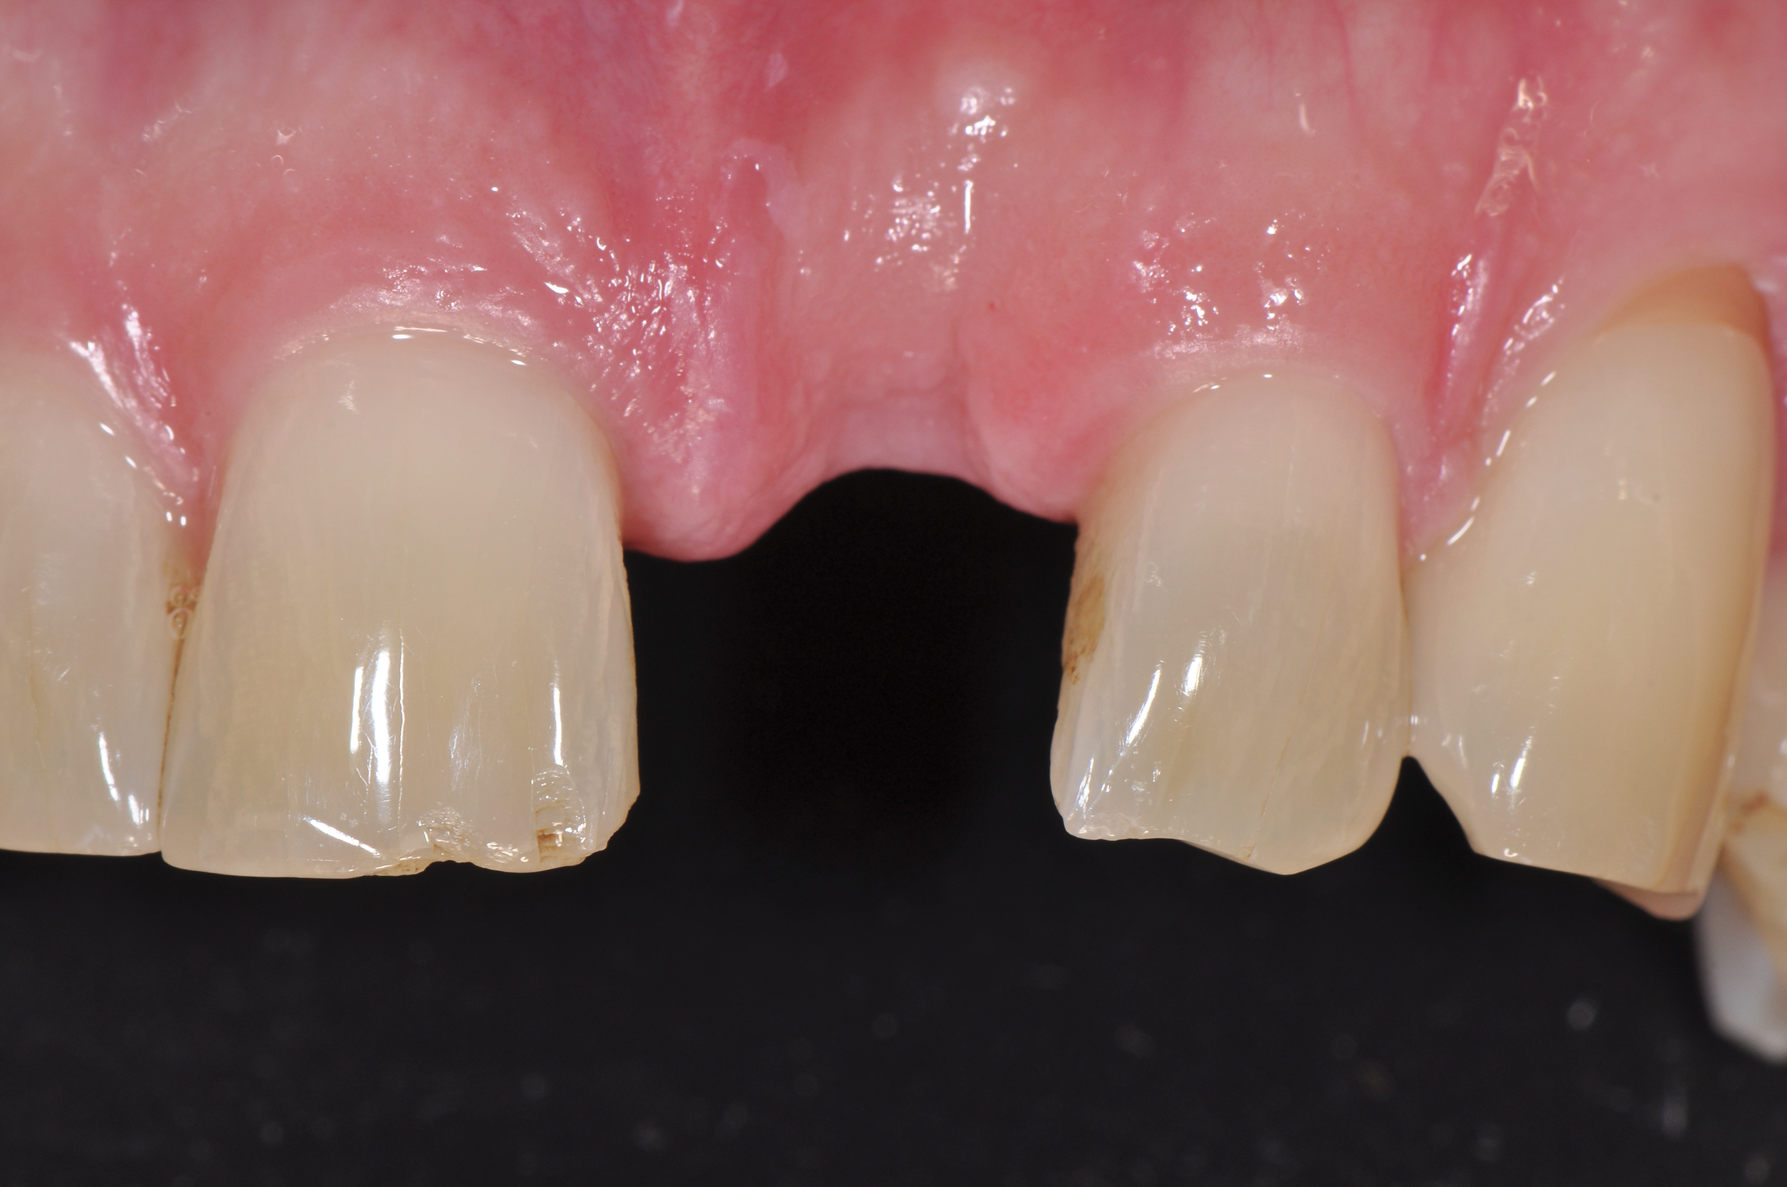

Still, as with titanium implants, undesirable recession with an exposed implant shoulder may occur in rare cases with ceramic implants. Nonetheless, from an esthetic point of view, this inflammation-free recession of the gingiva is likely to be tolerated much better by patients concerned with the dark margins of titanium implants (Figure 2).

Fig 2. Recessions in ceramic (left) and titanium (right) implants.